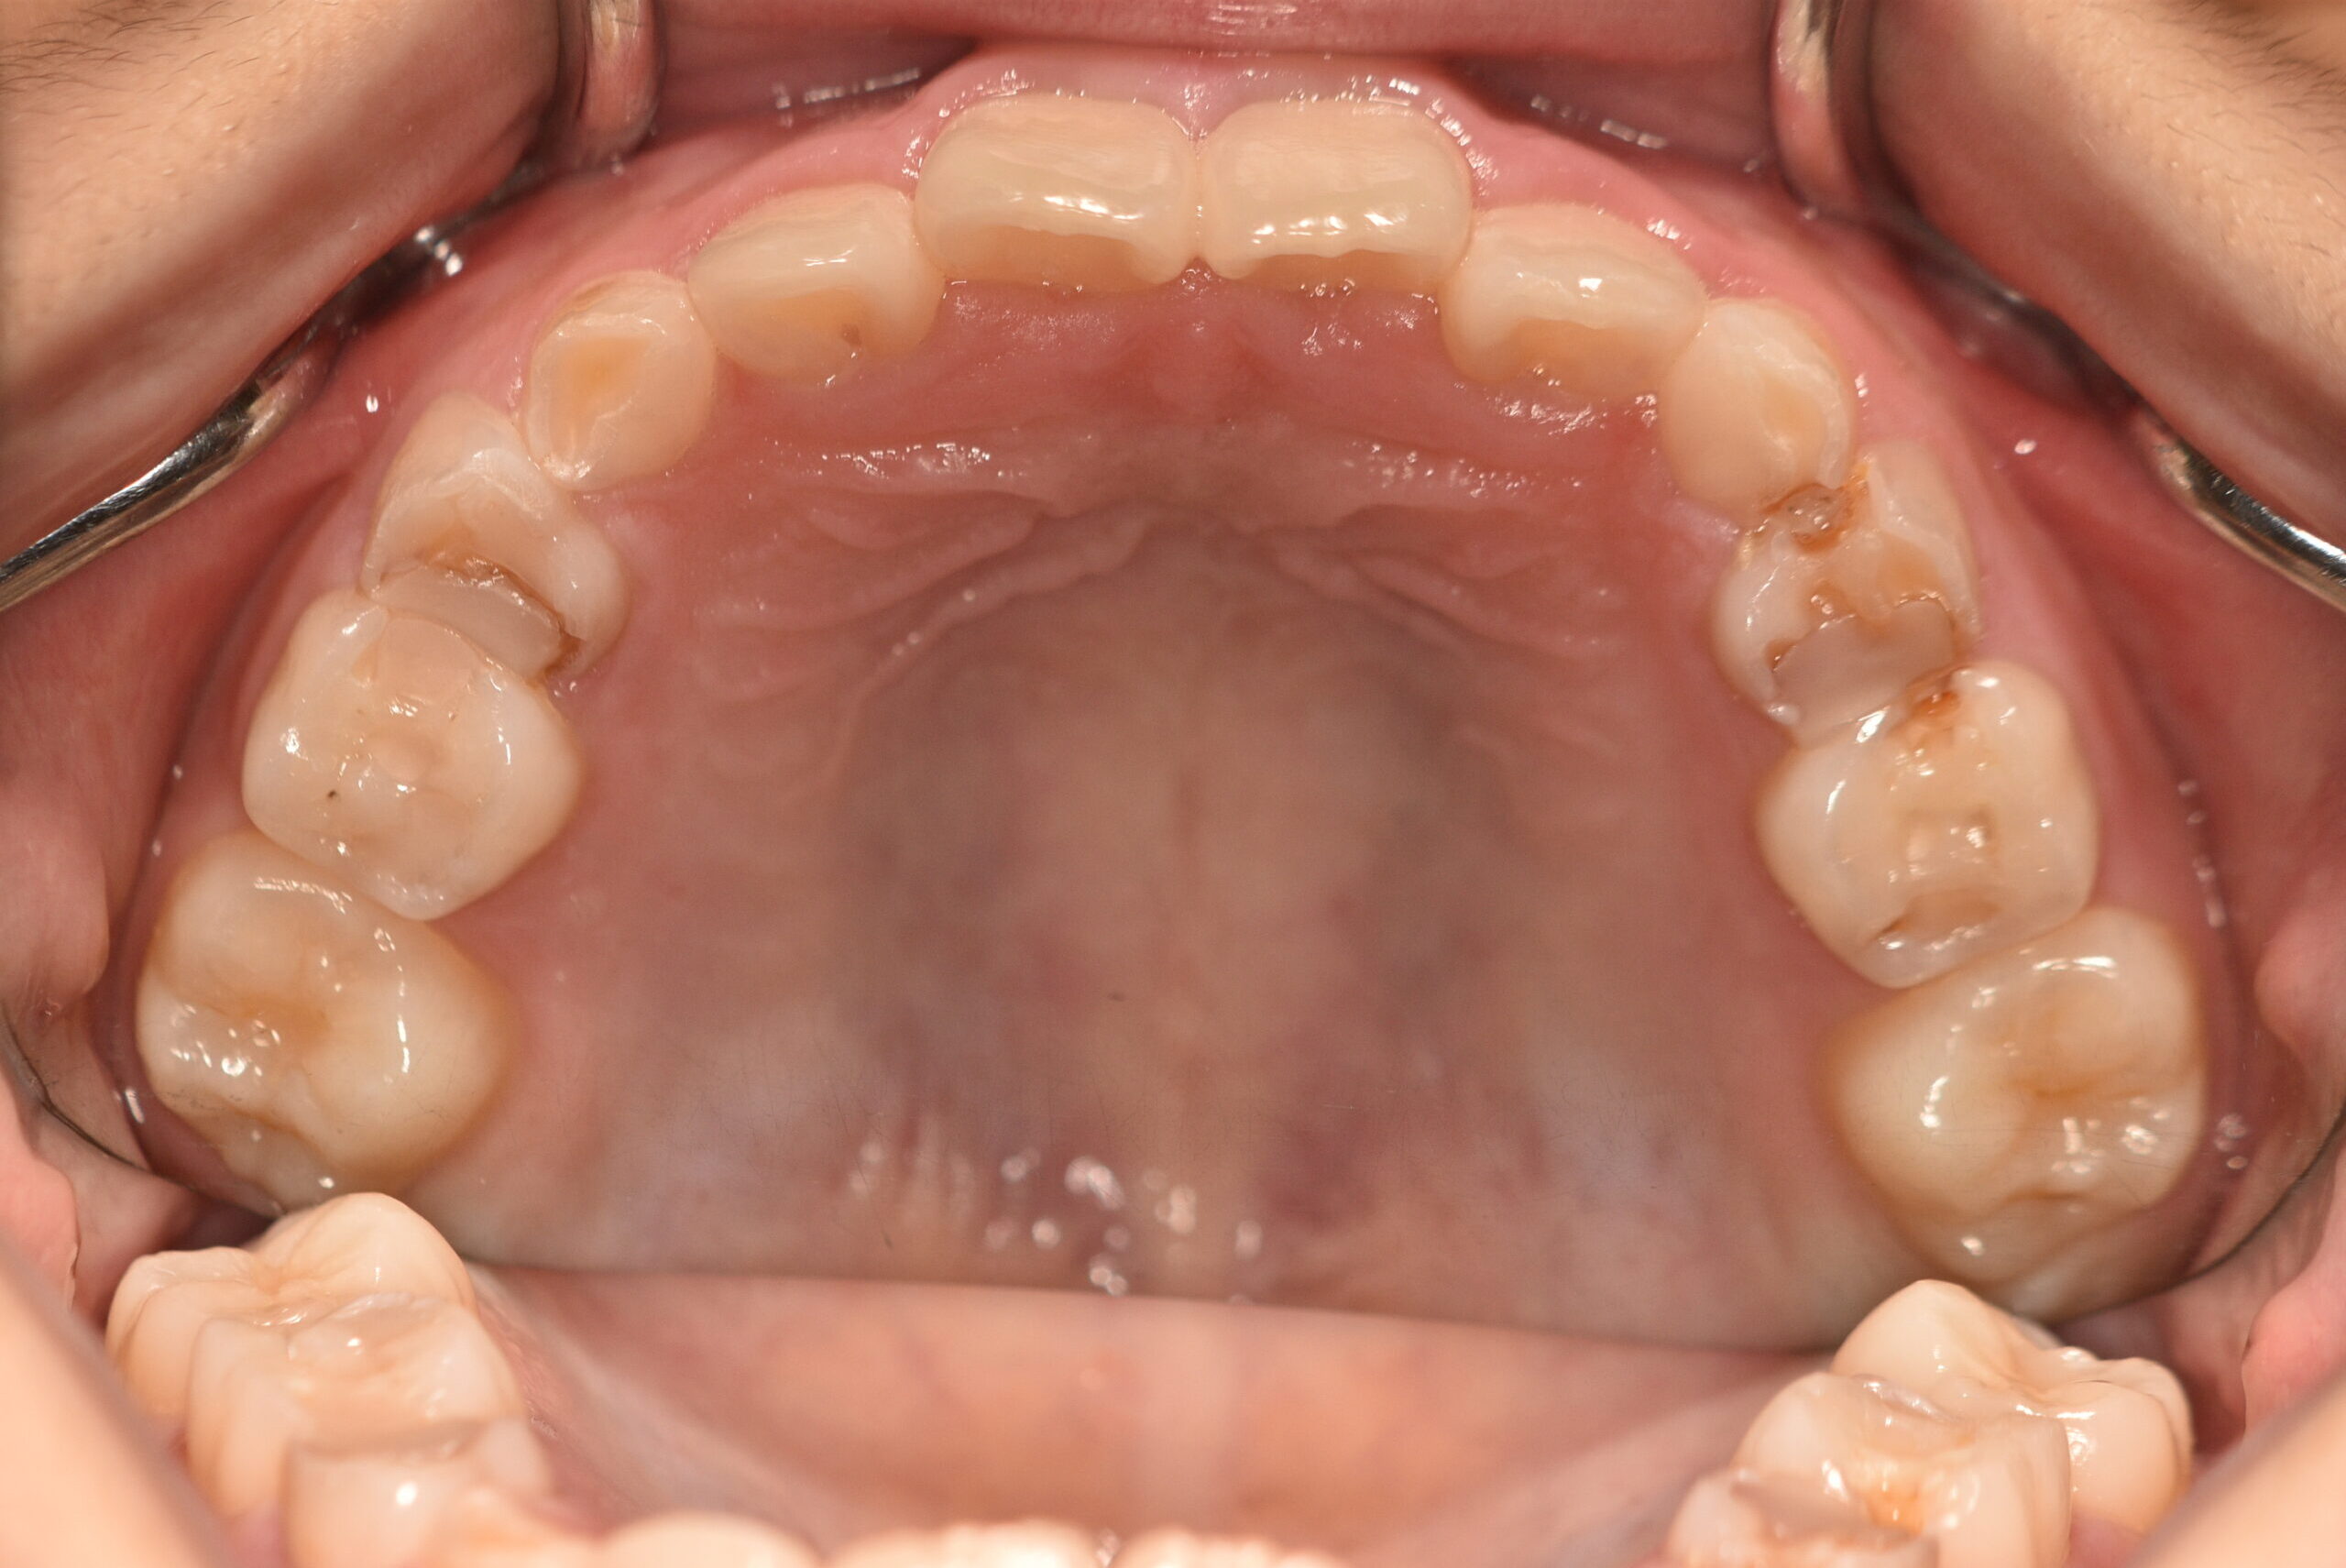

動的治療終了時

症例 症例 症例 症例 症例

永久歯列に交換後、非抜歯の上、セルフライゲーションブラケット装置(デーモンシステム)で歯の配列を行いました。

治療期間は、4年3ヶ月でした。